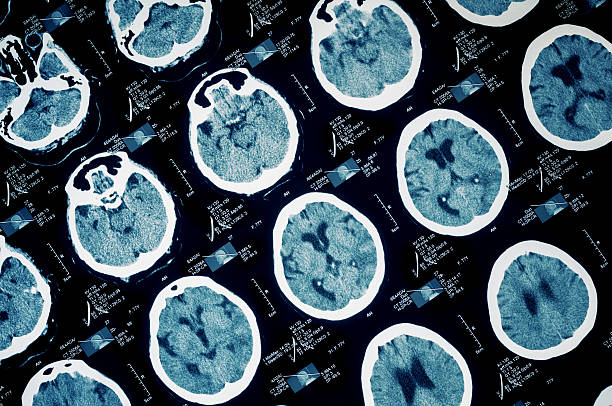

If you have been struggling to complete daily tasks or are unable to work due to traumatic brain injury (TBI), then you should consider applying for social security disability benefits.

- Gather All Medical Evidence Related To Your TBI – This should include your diagnosis, medical visits with your doctor, hospital stays, physical therapy, and other medical attempts to treat your traumatic brain injury.